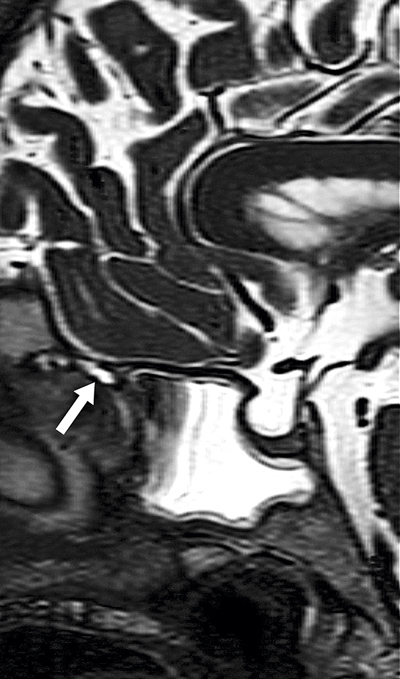

Figur 1. Magnetkamerabild (T2, fettsupprimerad) av främre del av skallen, sagittal vy. Bilden visar vätska i sfenoidalsinus samt misstänkt kanal med likvor (pil). Vid bläddring genom bildserien kunde den misstänkta kanalen följas från lamina cribrosa höger sida.

Efter 9 månader av fortsatt ensidig rinnande klar snuva och nu uttalat påverkat allmäntillstånd sökte patienten vård på en privat ÖNH-klinik. Vid fördjupad anamnes framkom att vätskan ur näsan framför allt kom då hon böjde sig framåt. Misstanke om likvorläckage väcktes och patienten remitterades till ÖNH-kliniken på Sahlgrenska universitetssjukhuset. Man beställde analys av beta-trace-protein i vätskan, vilket visade förhöjda nivåer (24,3 mg/l jämfört med 0,9 mg/l i serum från patienten). Fyndet talade för likvorläckage. En DT-sinus visade på vätskenivåer i sfenoidalsinus men ingen tydlig skallbensdefekt. MR-hjärna ingav dock misstanke om att läckaget kom från lamina cribrosa (se Figur 1). Patienten genomgick 2 endoskopiska operationer, utförda i samarbete mellan neurokirurg och ÖNH-kirurg. Först vid andra operationen, då ett fluorescerande ämne injicerades intratekalt inför operation, kunde läckagestället identifieras. Defekten tätades med hjälp av fett från låret och i samma seans lades ett lumbalt drän in. Patienten dränerades på 150–200 ml likvor per dygn i 5 dagar. Dränet avvecklades och patienten kunde skrivas ut. Patienten har därefter varit symtomfri och besväras inte längre av något läckage från näsan.